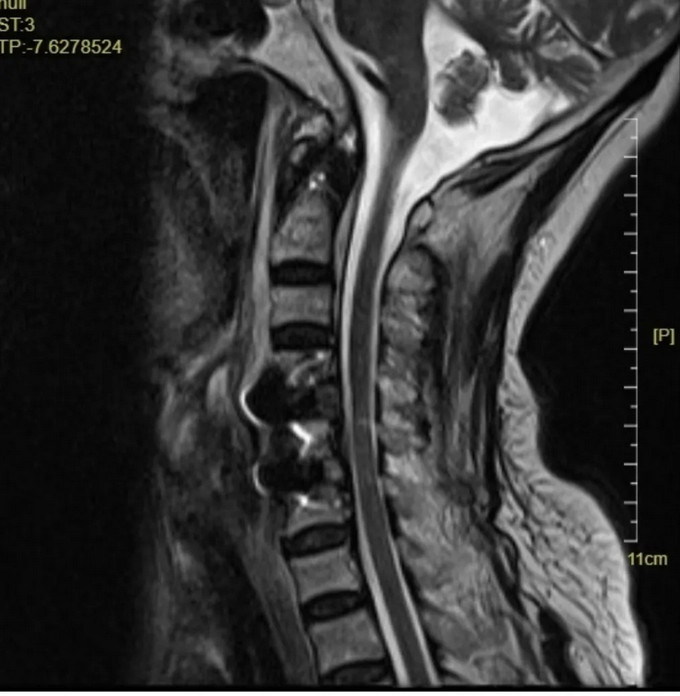

术前影像

颈椎MRI矢状位,可以看到患者的颈神经被明显压迫